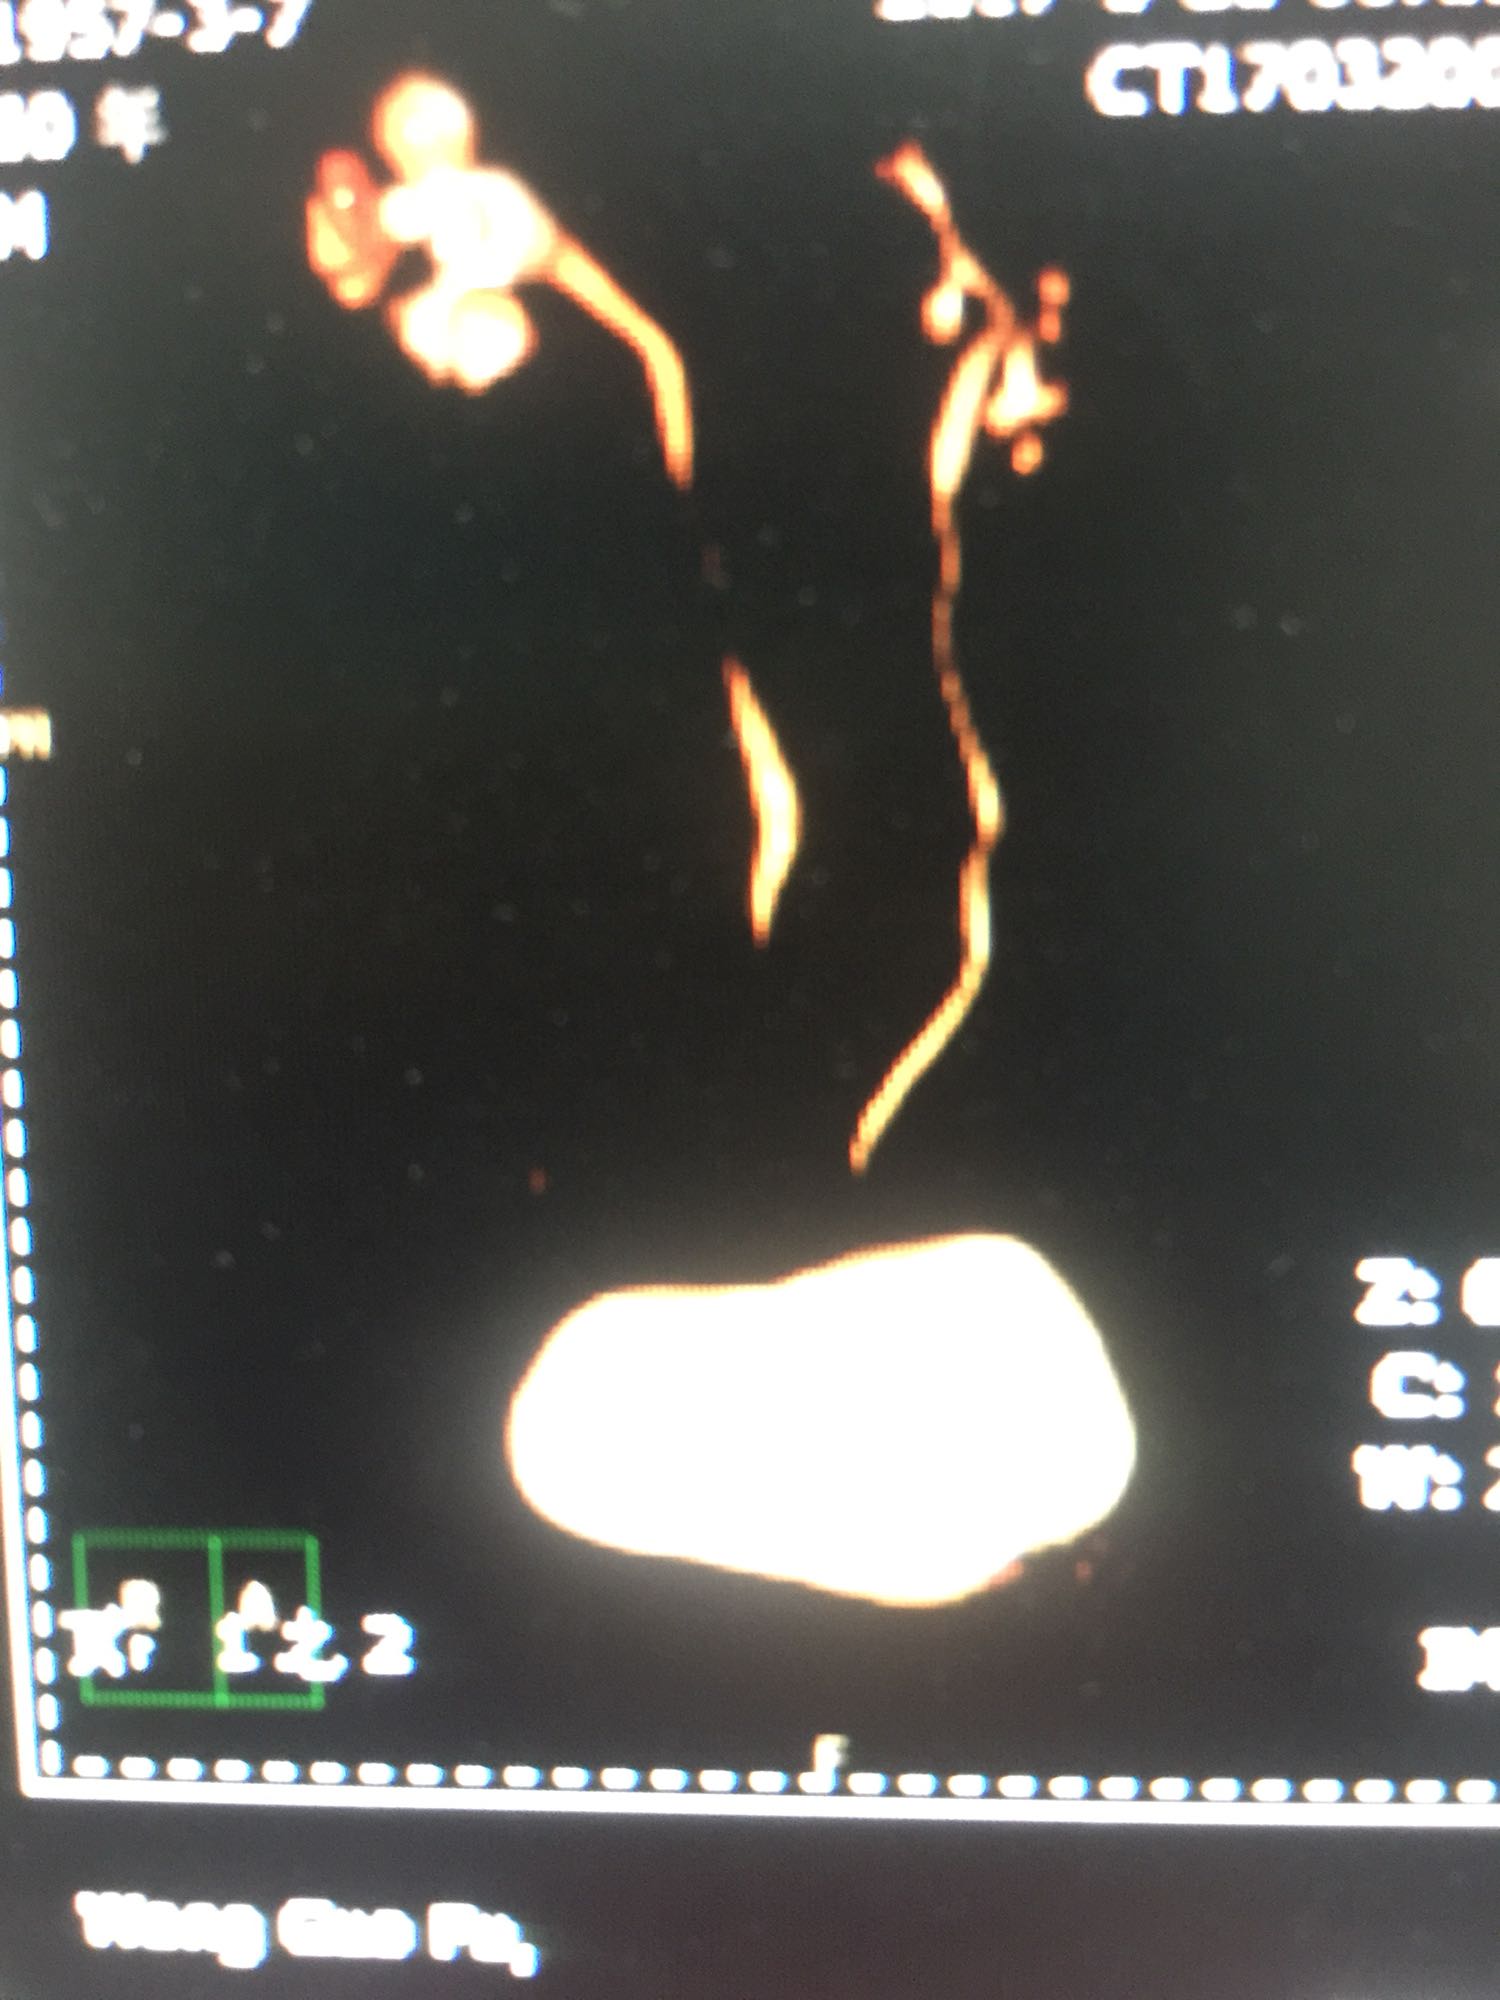

查体:双肾区无叩压痛,膀胱区无叩压痛,无叩浊,前列腺二度,质地中等,无压痛,无结节。CTU提示右肾铸型结石。ECTL 40,R14.5

右肾铸型结石 予以经皮肾碎石治疗,术后复查平片未见结石残留。

铸型结石以经皮肾手术作为主要的术式。但手术可能一次或多次进行。术后残留结石,术后复发等几率高。我们见过2月后几乎又长满的结石。